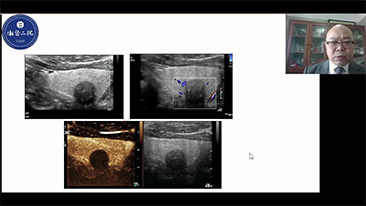

Inzichten

De medische omgeving van vandaag is complexer geworden, met een toenemend aantal moeilijke gevallen en meer werkdruk.